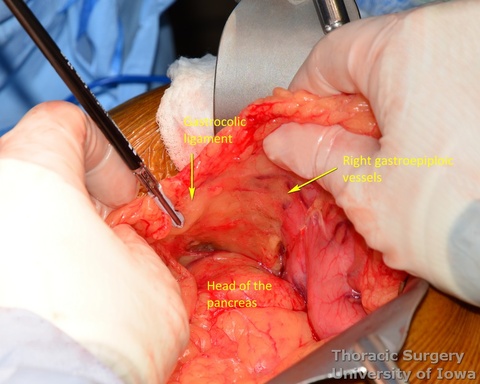

- The gastrocolic ligament is incised in its avascular portion between the terminal branches of the right and left gastroepiploic vessels, and the lesser sac is entered.

- The greater curvature of the stomach is then mobilized towards the pylorus, dividing the gastrocolic ligament no closer to than 1.5–2 cm to the right gastroepiploic vessels, while protecting the vessels with the fingers of the retracting hand. In morbidly obese patients the right gastroepiploic artery may not be visible or palpable. A Doppler probe is used then to identify its course and origin from the gastroduodenal artery.